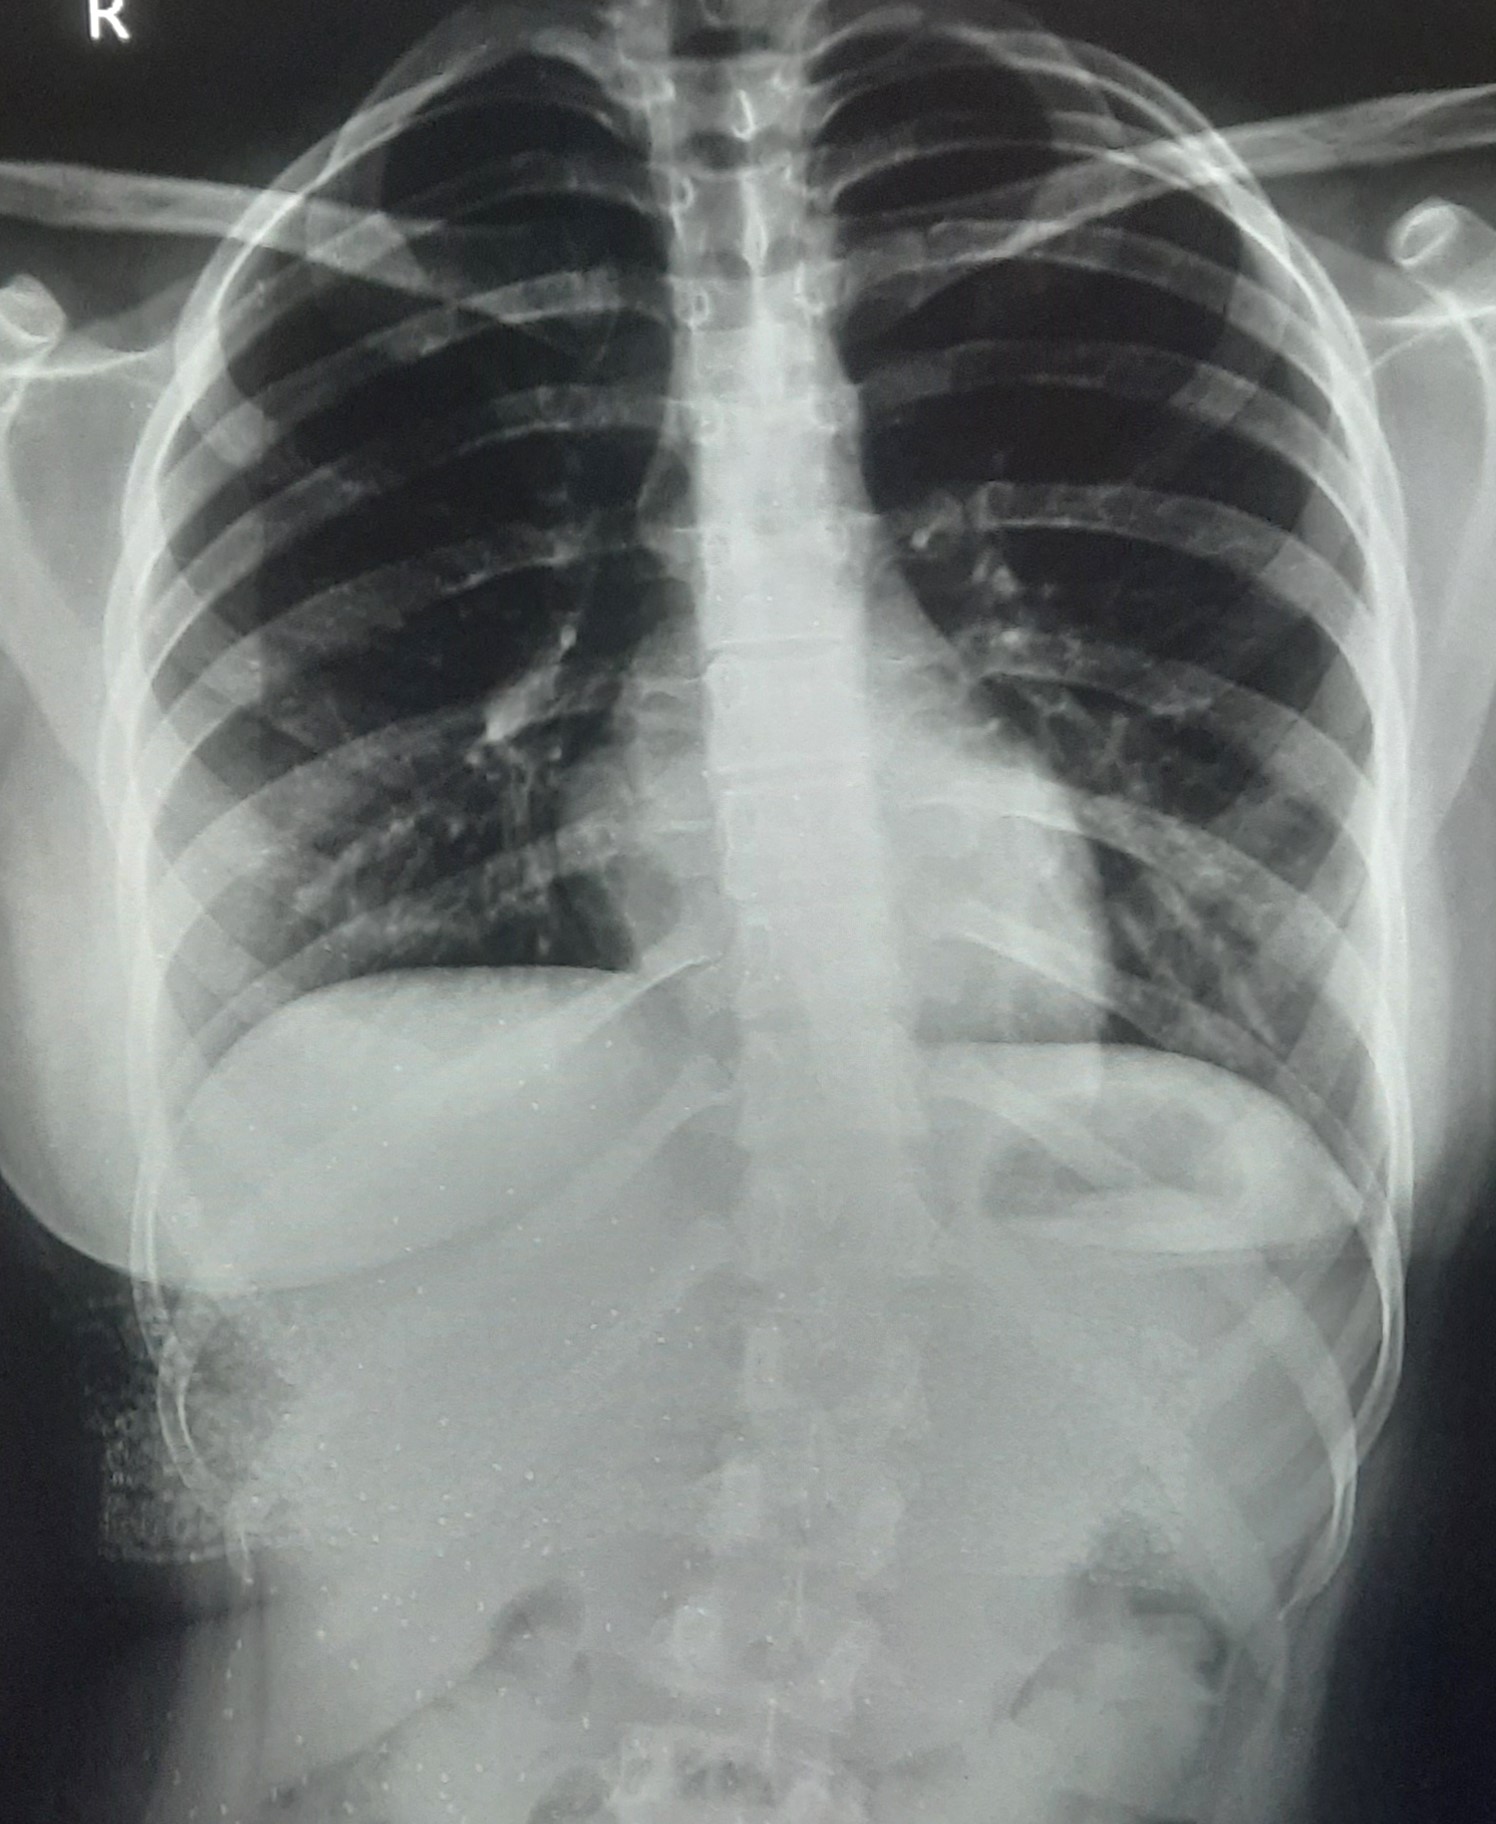

| 271 | IGGMC, Nagpur, Nagpur | P2 | 29-4201 | Abddul Qayyam | Consent taken on Paper | 75 Yrs. |

Provisional Diag : Upper Respiratory Tract Infection

Final Diag : FIBROSIS |

Non-TB Case (Confirmed) | RETICULAR OPACITIES NOTED IN PREDOMINANTLY IN UPPER ZONE OF RIGHT LUNG PARENCHYMA | Abnormality visible on x-ray |